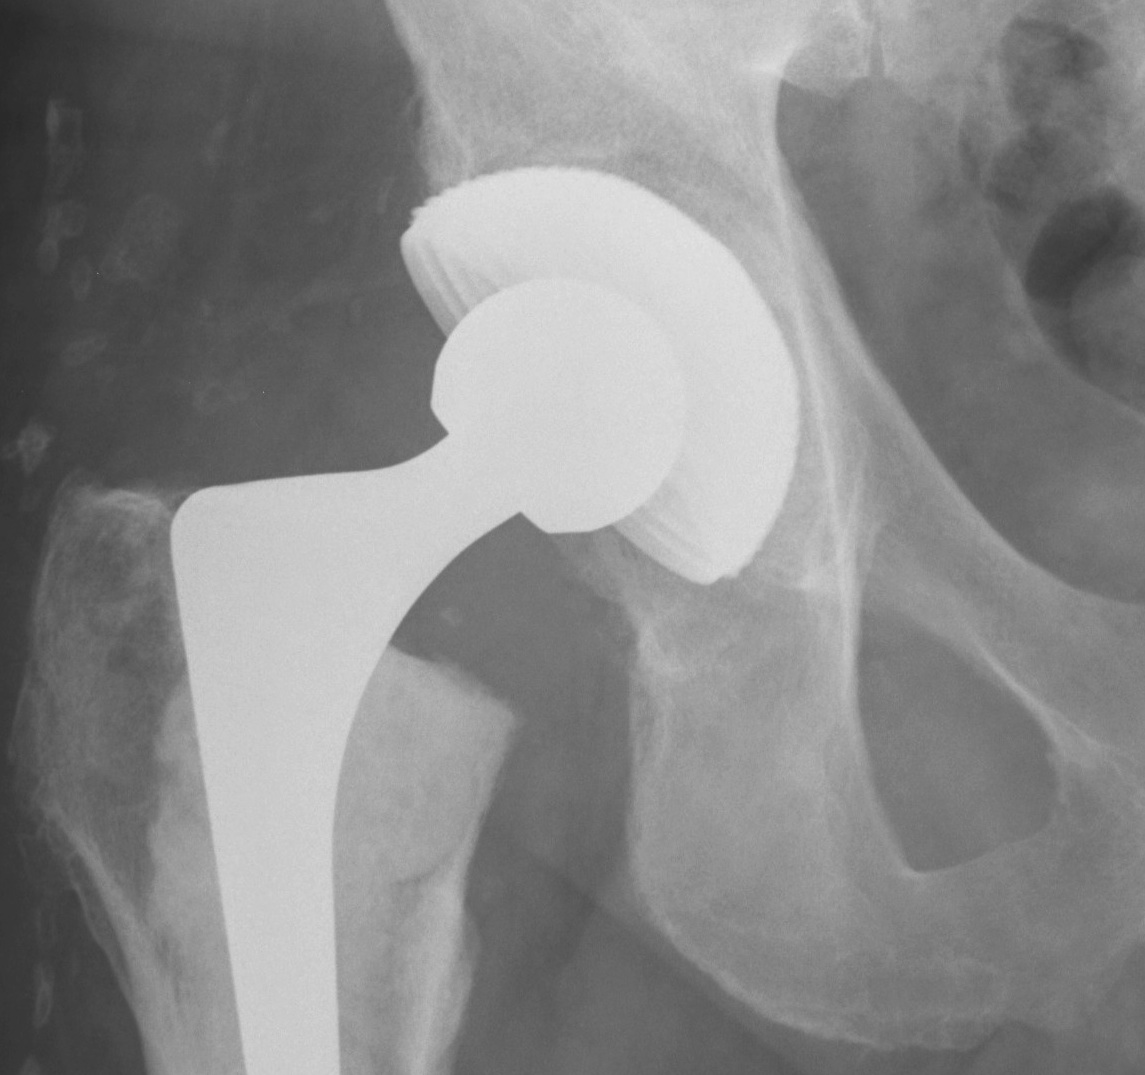

Type IIIA defects

Type IIIA

- Rim < 50% missing, > 40% host bone contact

- want to reconstruct defect but don't need cage

1. Uncemented rim fit cup / screws / Structural bone graft

Indications

- defect superolateral rim < 50% to support cup

- > 50% host bone contact

- allograft will not grow onto uncemented cup

- allograft to reconstuct defect

Technique

- femoral head allograft reconstruction (no 7 shape)

- fix with 6.5 mm screws

- tap first to prevent fracture

- ream into bone

3. Trabecular metal components

New material made of element tantalum

1. Interconnecting porous material

- 80% porous

- allows 2-3 X bony ingrowth

2. Less stiff

- improved remodelling of BG underneath

3. High cancellous bone coefficient of friction

- excellent initial stability

- may need less than traditional 50% host bone contact

- may not need screws

Ream host bone for press fit cut

- trial then secure trabecular augment with screws

- press fit cup with cement between augment and cup

- screw augmentation of cup